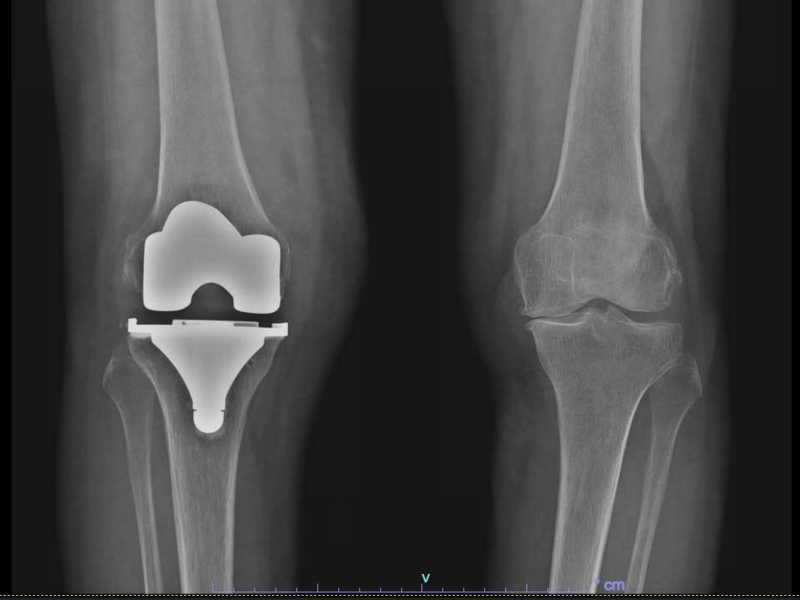

Les composants d'une Prothèse Totale de Genou

Cette intervention consiste à remplacer l’articulation du genou par des composants artificiels qui reproduisent l’anatomie initiale du genou. Le type d’implant doit être adapté à chaque cas particulier, en ce qui concerne sa forme, sa taille, la nature des matériaux entrant dans sa composition, son revêtement extérieur et la technique chirurgicale à employer.

Généralement, une prothèse de genou se divise en trois parties : un insert fémoral, une embase tibiale surmontée d’un polyéthylène et un resurfaçage de la rotule par un polyéthylène. Les composants sont le plus souvent fixés par du ciment.

La prothèse que nous mettons en place est un implant en alliage CrCoMo (implant fémoral) et titanium (implant tibial).

Vous serez régulièrement revu en consultation lors de visites de contrôle, à un mois, trois mois, six mois et à un an, puis tous les deux ans avec un examen clinique et radiographique.